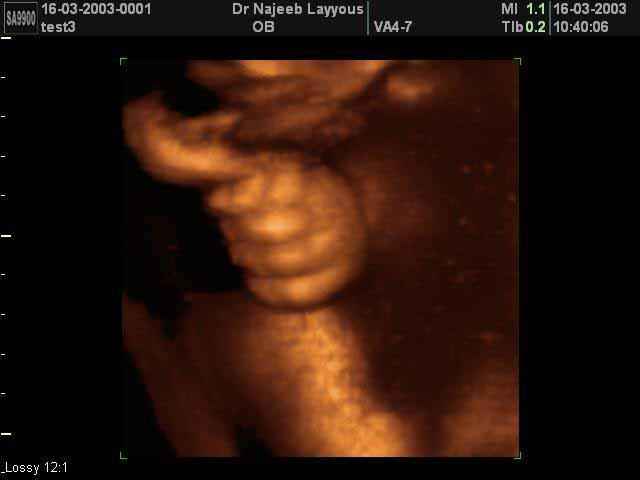

- صور لأطراف الجنين

- صور لتصرفات الجنين داخل الرحم

صور لأطراف الجنين بجهاز الالتراساوند ثلاثي الأبعاد | الدكتور نجيب ليوس